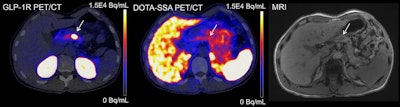

Images of exendin PET/CT, DOTA-SSA-PET/CT, and CE-DWI-MRI (T1-weighted precontrast) of a study participant. Location of insulinoma in pancreas body is indicated with arrows. Only exendin PET/CT was true positive in this patient.Image available for republishing under Creative Commons license (CC BY 4.0 DEED, Attribution 4.0 International) and courtesy of the Journal of Nuclear Medicine.

In addition, in 13% of patients, a correct diagnosis was only reached after exendin PET/CT, the researchers noted.

Ultimately, the combination of exendin PET/CT and CECT provided the correct diagnosis in 53 of 54 participants in the study, the researchers noted.

“Exendin PET/CT combined with CECT could provide a one-stop-shop procedure for insulinoma localization, greatly reducing and simplifying the imaging work-up for the large majority of patients,” the researchers concluded.